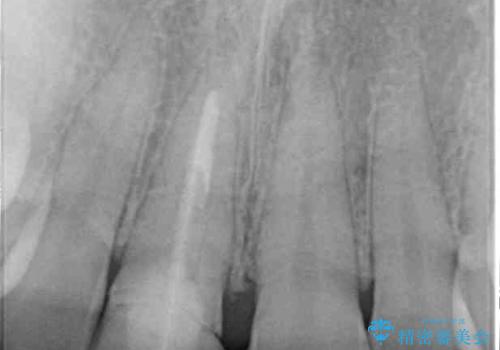

- 近医にて被せた前歯のクラウンの色の違いを気にして来院された患者様です。

オーダーメイドのオールセラミッククラウンにて補綴することとしました。

元々すきっ歯であったため、隙間を全て埋めると左右で大きさがアンバランスとなることが懸念されました。

違和感のない程度に隙間を小さくして、自然な見た目に仕上げました。